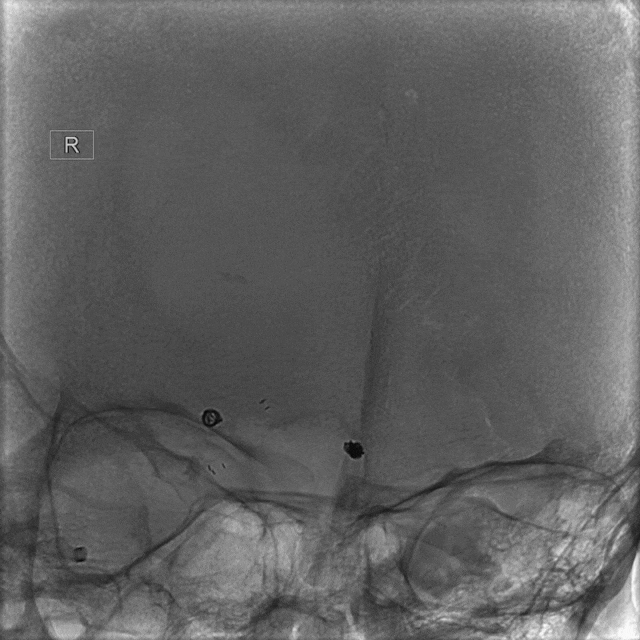

左侧颈内动脉造影

右侧颈内动脉造影

双侧椎动脉造影

压颈造影及压颈3D